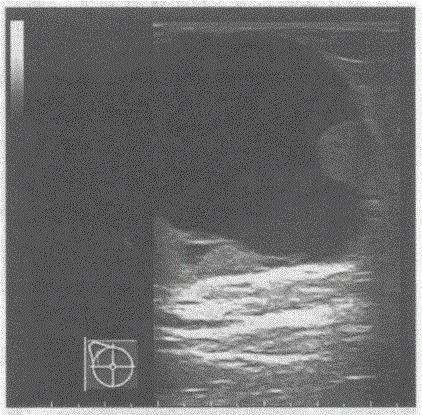

问题 临床资料:女,49岁,自诉右乳触及肿物2年余。 临床物理检查:右乳头外侧可扪及一肿物,质软,边界清晰。 超声综合描述:右乳头外侧可见4.8cm×4.7cm无回声区,边界清晰,形态规则,内可见乳头状中等回声突起。 超声提示:

选项 A.右乳腺假体植入 B.右乳腺囊肿 C.右乳腺脓肿 D.右乳腺乳头状囊腺瘤

答案 D